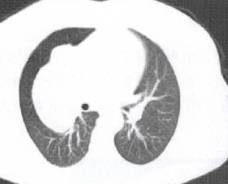

常位于上叶尖后段、下叶背段,因肺泡壁破坏,无空泡征或支气管充气征,增强检查内 部为低密度无增强影,肉芽肿成分为主亦可见增强。病灶边缘光滑,一般无分叶及毛刺,少 许有多个增殖性病灶融合形成者,可不规则成分叶状。病灶内多可见钙化,CT值多高于 160Hu、周边多有卫星灶,局部胸膜增厚多见,长期随访观察,一般增长不明显,病程较 长,肺内常另有散在性结核病灶。但病灶如表现不典型,呈孤立肿块影,有时与肺癌难以鉴 别(图9)。 医学百科网 | YxBaike.Com